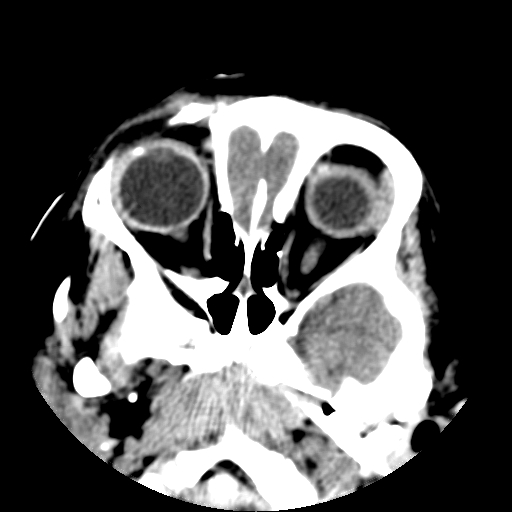

以下是引用深泽交通医院在2009-10-16 8:25:00的发言:[br]右眼环出血伴异物

以下是引用卜一在2009-10-16 15:01:00的发言:[br]右眼球挫裂伤伴异物!

以下是引用拾荒者在2009-10-17 18:38:00的发言:[br]鼻面部皮下积气,右侧睑缘及眼球壁高密度异物影,左侧眼球壁晶状体内侧缘处是圆形低密度影。低密度异物?应提请眼科医生注意。